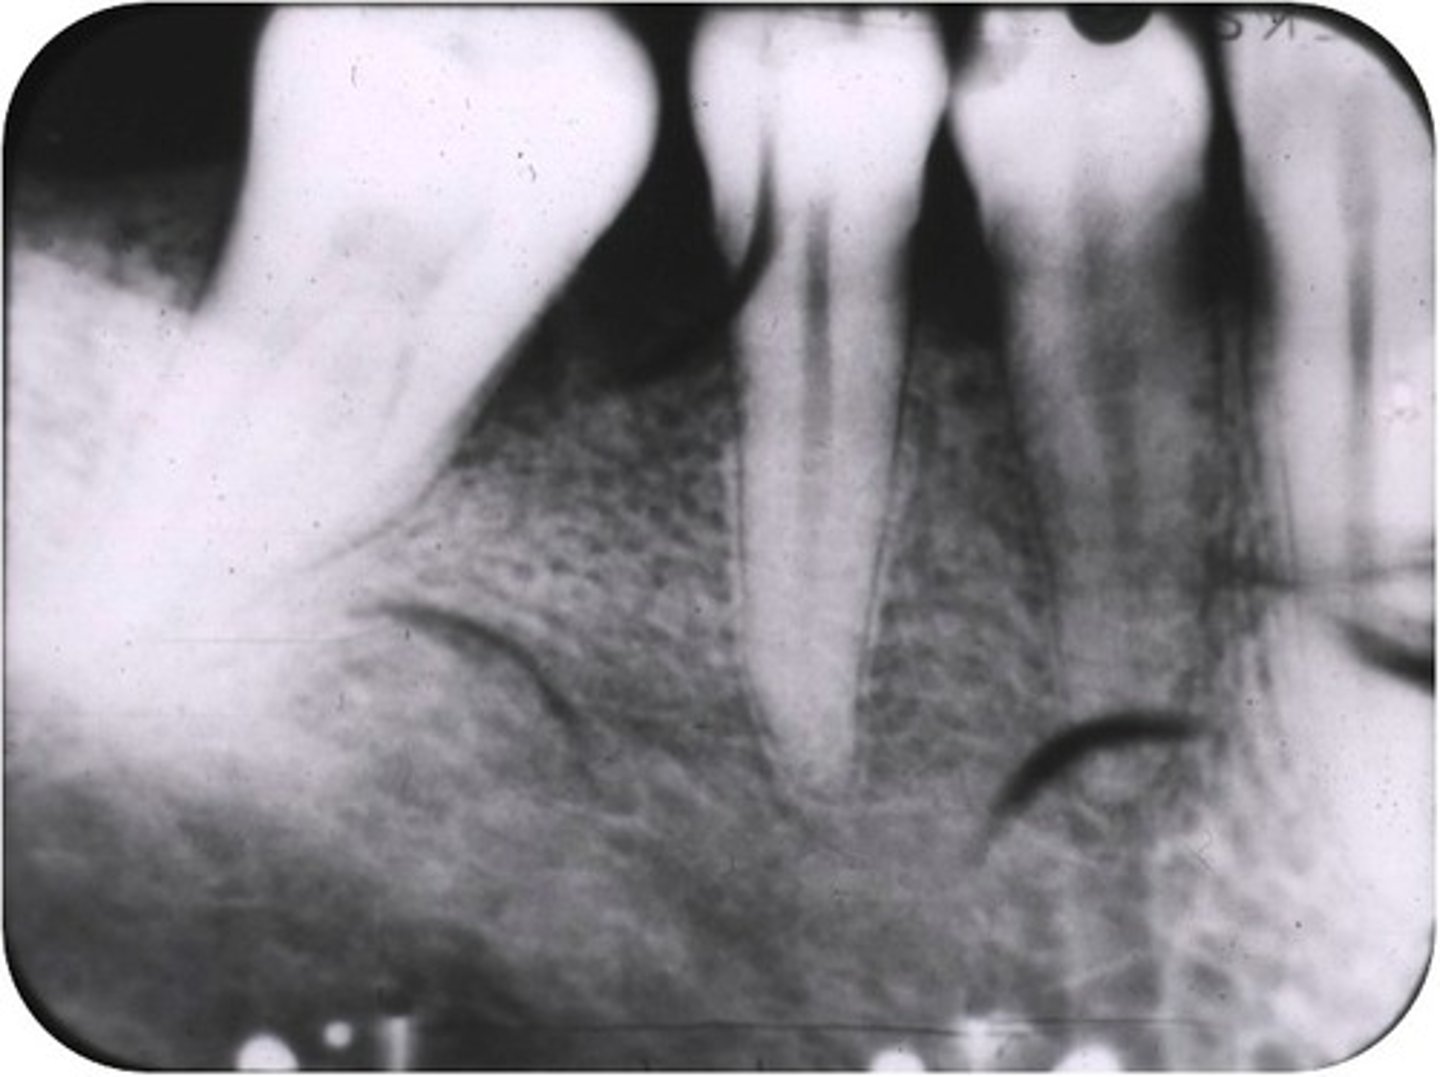

Elongated images

Long distorted teeth. Too little vertical angulation.

<p>Long distorted teeth. Too little vertical angulation.</p>